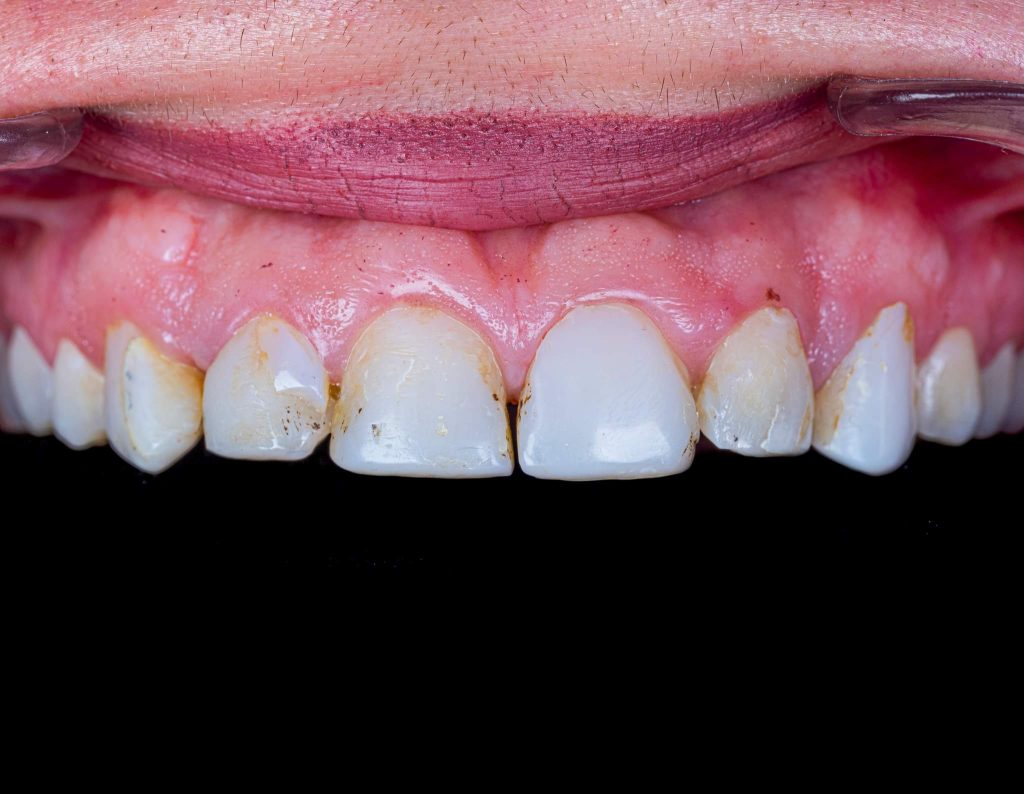

The case presented in this case report is for a 27-years-old female patient with a chief complaint of aesthetic correction for her smile. The patient was unhappy with her smile. After clinical examination, there were previous old composite veneering done poorly and incorrectly to close the multiple interdental spacing. After discussing the various treatment options (i.e., orthodontic treatment, direct, or indirect veneers), indirect ceramic veneering was selected. The step-by-step treatment protocol is presented in the images below.